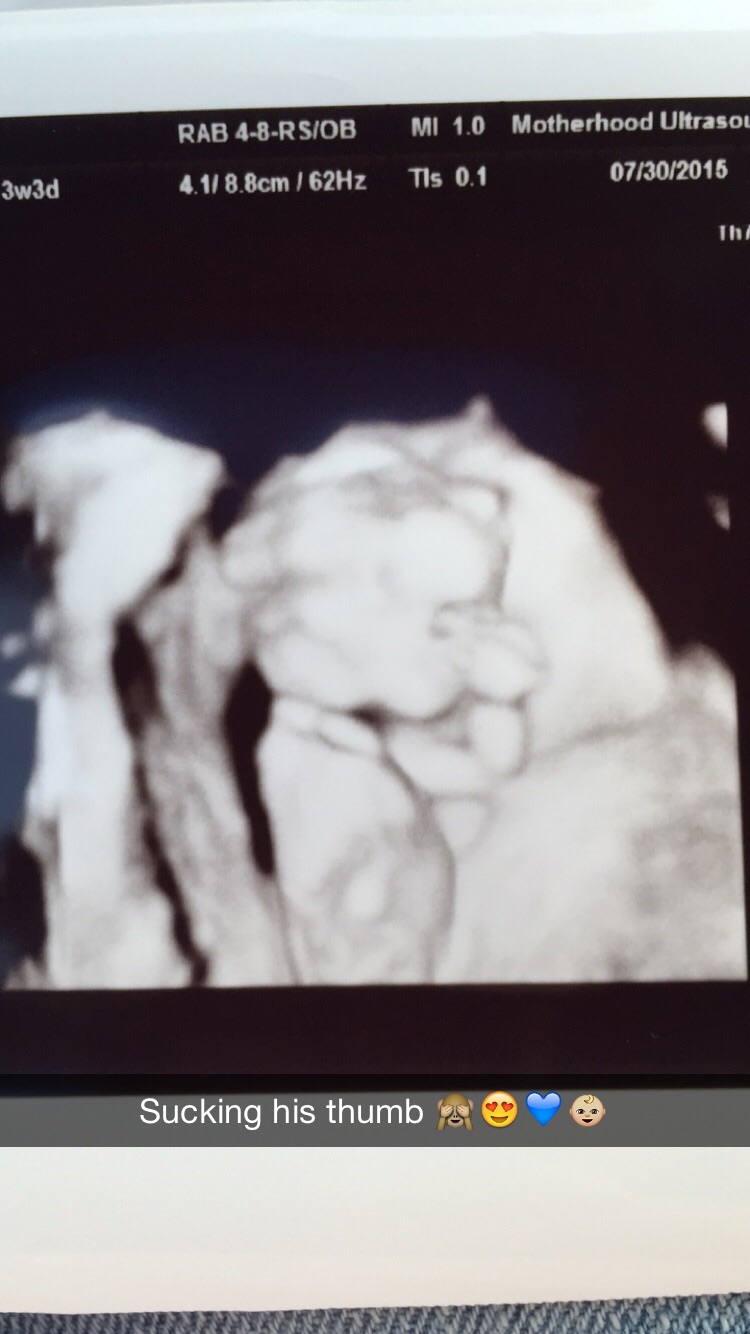

Had our second ultrasound baby was super active and was sucking its thumb ! Heartbeat was 156 Bpm.Ultrasound taken at 12 wks 4 days and today I'm 13 weeks ! Does anyone have a gender guess for my little nugget ? ❤️